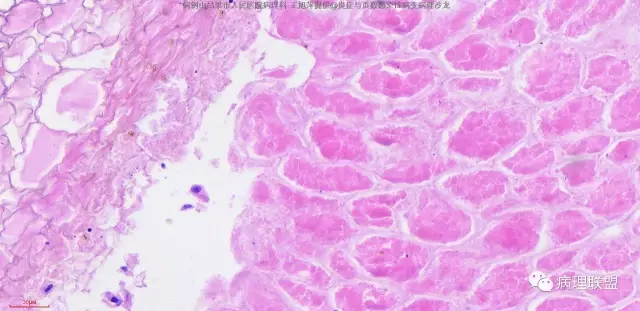

病人,男,60岁,腹股沟疝强行复位致肠管破裂,术中于肠系膜根部见结节一枚送检,肉眼灰红结节一枚,直径0.5cm。该病人于十年前曾行直肠癌根治术,麻烦各位老师,肠系膜结节考虑什么。(病例由吕梁市人民医院病理科 王旭萍提供,致谢!)